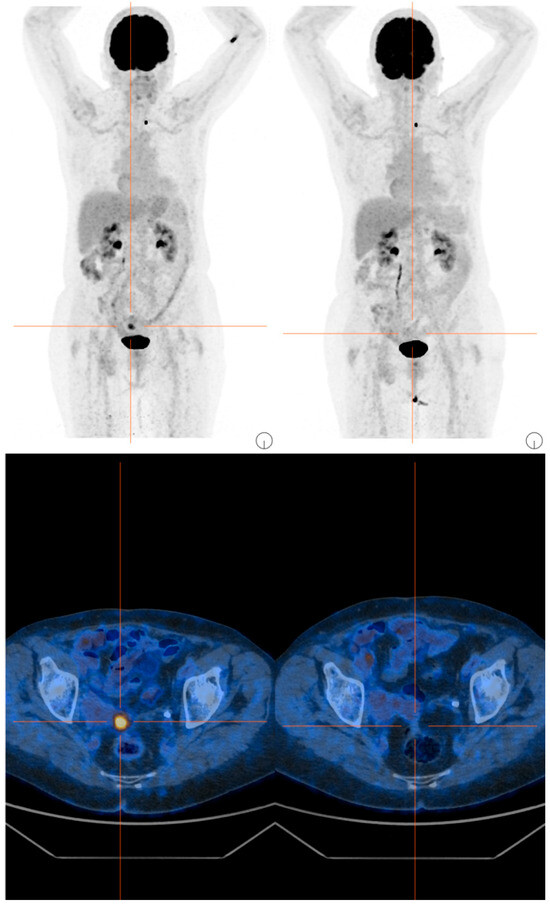

Breast cancer rarely metastasizes to the parotid gland. Early recognition in patients with a history of malignancy is critical for timely diagnosis and treatment. We report the case of a 60-year-old female who presented with a two-month history of a left periauricular mass, [...] Read more.

Breast cancer rarely metastasizes to the parotid gland. Early recognition in patients with a history of malignancy is critical for timely diagnosis and treatment. We report the case of a 60-year-old female who presented with a two-month history of a left periauricular mass, 18 months after completing treatment for breast carcinoma. Despite the patient’s oncologic history, initial evaluation by our maxillofacial surgery service showed no evidence of distant metastasis, and we initially ruled out metastatic disease. Clinical evaluation, contrast-enhanced computed tomography (CT), fine-needle aspiration cytology (FNAC), PET-CT, and histopathological analysis were performed. Given the persistent and progressive nature of the mass, surgical excision was undertaken to obtain a definitive diagnosis and provide local control. Immunohistochemical analysis of the resected mass and adjacent node confirmed metastatic breast carcinoma infiltrating the parotid parenchyma and an intra-parotid lymph node, with strong positivity for progesterone receptor (PR) and carcinoembryonic antigen (CEA). Unfortunately, several months later, the patient developed pulmonary metastases and subsequently died. Full article